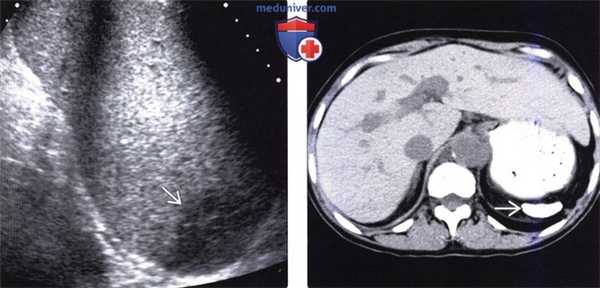

(Левый) При энергетической УЗ-допплерографии селезенки в продольной плоскости определяется центральная четко отграниченная клиновидная область относительной гипоэхогенности . В зоне инфаркта регистрируется ослабленный (но не отсутствующий) сигнал энергетического допплера.

(Правый) Пациент с последней стадией поражения печени и портальной гипертензией, массивным асцитом. КТ с контрастным усилением. На коро-нальной томограмме той же зоны определяется спленомегалия и центральный инфаркт селезенки. Наблюдается полостчатый артефакт, вызванный металлической эмболизирующей спиралью (после терапевтической эмболизации селезеночной артерии).

(Левый) При УЗИ в черно-белом режиме видна округлая зона полярного инфаркта селезенки. Гипоэхогенная зона инфаркта имеет четкие края. При цветовой допплерографии (не показана) в зоне инфаркта отмечается отсутствие кровотока.

(Правый) Показан разрыв селезенки, симулирующий инфаркт: четко отграниченная гипоэхогенная лентовидная зона, тянущаяся в субкапсулярную область. При дифференциальной диагностике важнейшее значение имеет факт травмы в анамнезе. У пациентов с тупой травмой живота из интраперитонеальных органов наиболее часто повреждается именно селезенка.